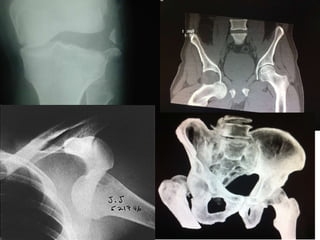

Directa relación con  accidentes de tránsito 50% de pctes sufre fractura en otra zona  al momento de la luxación . Luxación de Cadera Luxación  posterior  en la más frecuente (85-90%) Lesión del  N. Ciático  en el 10-20% de las Luxaciones posteriores.

Rx. Pelvis AP, Rx lateral de la cadera afectada. Rx Oblicuas TAC Pelvis Luxación de Cadera Estudio

Osteonecrosis:  5-40%, mayor riesgo a mayor tiempo entre la luxación y reducción. Síntomas tardíos hasta 5 años post trauma. Luxación de Cadera Complicaciones J. Orthop Trauma . Vol 12 No. 4 p.223-229 Artrosis post traumática:  complicación más frecuente .  Mayor riesgo cuando se asocia a fracturas de acetábulo.

Lesion Neurovascular:  N. ciatico . 10 . 20 % de las luxaciones posteriores. N. femoral : en luxaciones anteriores. Enf. Tromboembolica. Osificación heterotopica : 2% de los pacientes. Luxación de Cadera Complicaciones